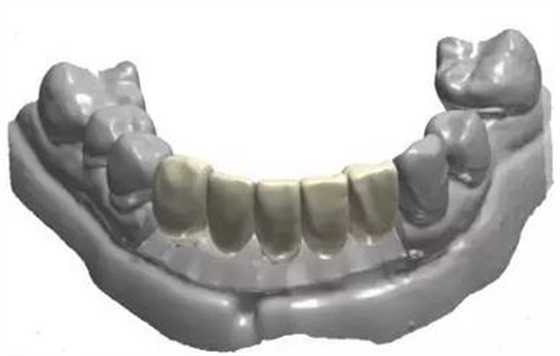

利用3shape導(dǎo)板軟件虛擬排牙

以修復(fù)為導(dǎo)向規(guī)劃植體

通過3Shape Dental System軟件同期設(shè)計(jì)臨時(shí)冠